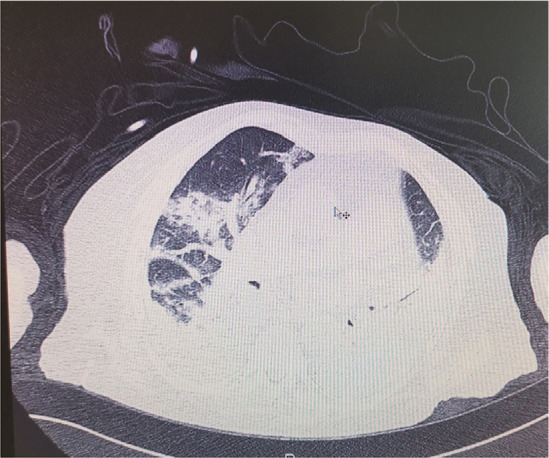

Case presentation: We present a case of a 77-year-old woman, who experienced a major flare, involving renal impairment, cardiorespiratory deterioration and pleuritis, along with signs of haemolytic anaemia, three weeks after a severe CDI. She received corticosteroids, rituximab (RTX), and cyclophosphamide (CYC), but the outcome was still fatal.